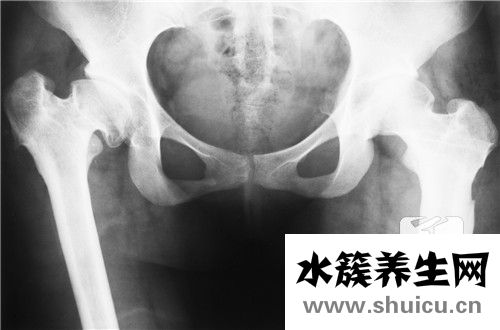

髖關節滑膜炎是一種不治之癥,由先天性髖關節發育不良引起,會導致骨骼畸形,進而導致嬰兒骨盆發育不良和髖關節疼痛。需要孩子環節的物理糾正,錯過了最好的時間也無法治愈。根據兒童髖關節滑膜炎的病因,可以掌握以下幾點,做好適當的治療。

最先,先天的髖關滑膜炎,便是一種小寶寶的髖關位置發育不全的病癥,是很廣泛的嬰兒階段四肢產生畸型的一種病癥,是不可以治愈的。因為先天的髖關滑膜炎與因創傷導致的發炎,是有較為大的差別。得了先天的髖關滑膜炎的小寶寶實際上不容易感覺有痛感,對于蹲下、站立起來這種姿勢也都沒一切艱難。

次之,小嬰兒出生后的第一年盆骨層面的生長發育非常快速,伴隨著小寶寶的漸漸地發展,盆骨生長發育基本定形之后便會越來越較為無法治療了。而有一部分本性的髖關滑膜炎的小寶寶剛好便是由于發覺的較為晚了,因而就錯過能夠 做物理學性層面對策開展糾正,只有根據接納手術治療的復位醫治。所以說,得了髖關滑膜炎一定要引起重視。

1、小孩髖關一過性滑膜炎是由于運動過量而造成的。本病大部分產生在3-10歲時,因為小孩股骨頭生長發育尚不成熟,關節軟骨較松馳,下肢一旦過多外旋,如從高空往下彈跳,或站不穩導致下肢外展臺扭到,或過多蹦跳疲勞使關節軟骨遭受拽傷,或關節軟骨被擠壓成型等便會造成髖關滑膜炎。

2、除開與運動過度不善相關,一過性滑膜炎的發病原因還與病毒感染感染、外傷、病菌感染相關。大部分患者病發忽然,約有過半數患者發病前身患呼吸道感染、中耳炎等感染病歷。